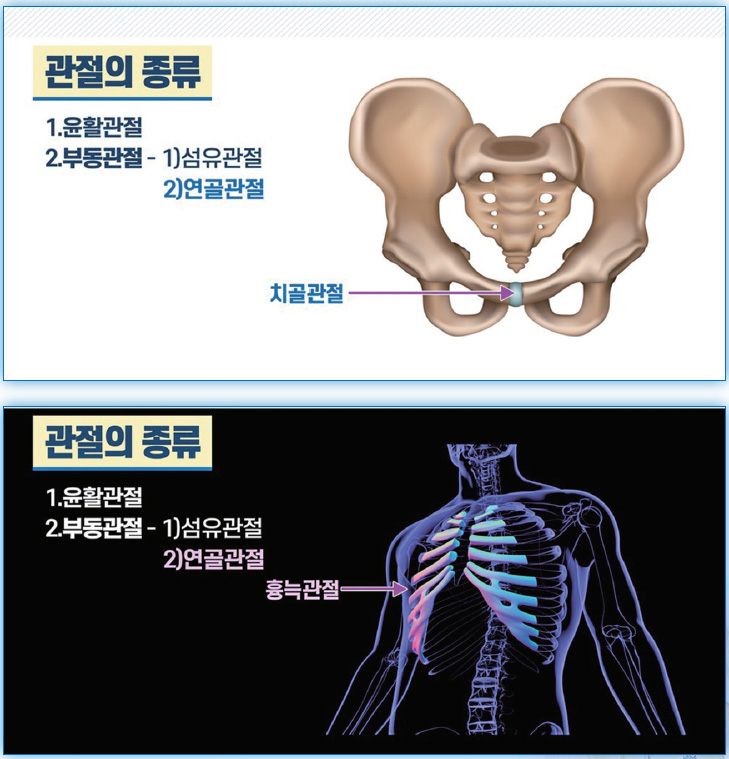

관절의 종류를 보면 크게, 움직일 수 없는 부동관절不動關節(Synarthrosis)과 움직일 수 있는 가동관절可動關節(Diarthrosis)로 나눠집니다. 움직일 수 없는 부동관절은 다시 두 가지로 나눠 볼 수 있는데요. 섬유관절纖維關節(Fibrous joint)과 연골관절軟骨關節(Cartilaginous joint)입니다.

- 부동관절② 연골관절

연골의 길이가 짧아 가동력이 전혀 없이 강하게 붙어 있는 치골관절恥骨關節도 있으며, 가슴뼈 흉골과 갈비뼈 늑골 사이의 연골은 길어서 약간의 움직임이 있을 수 있죠. 약간 확장하며 한숨을 크게 쉴 수 있는, 약간의 움직임이 있을 수 있는 흉늑관절胸肋關節도 연골관절에 해당됩니다.